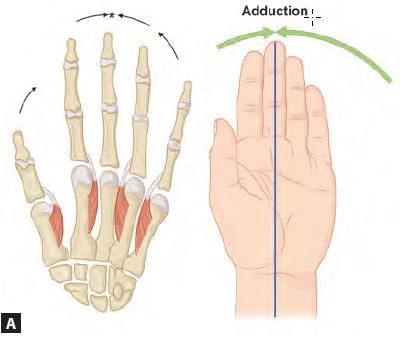

Which of the following finger has two dorsal interossei? (AIIMS May 2019)